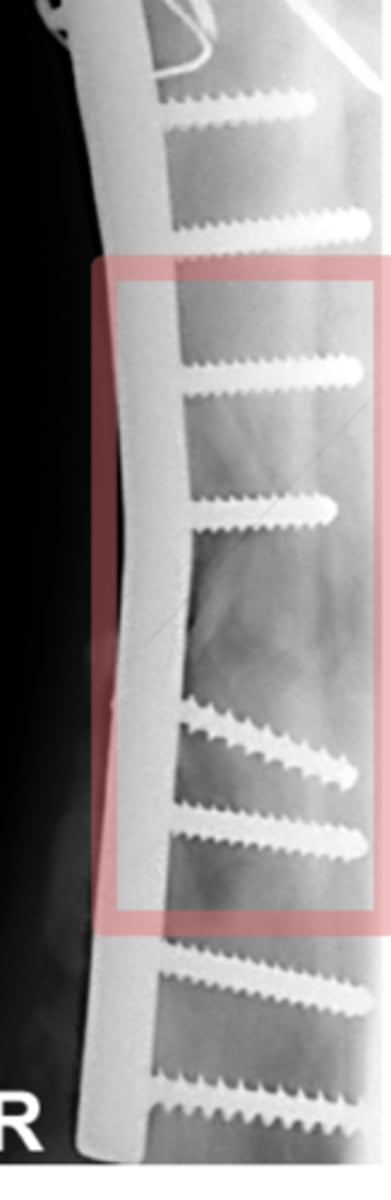

Identify the pathology?

Thermal necrosis - white halo around implant